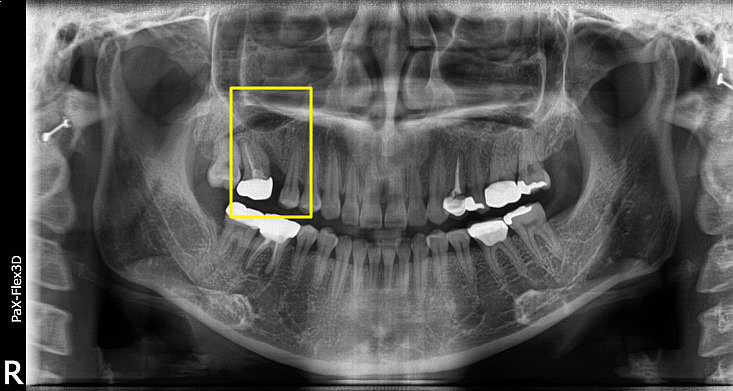

| 심각한 염증으로 발치후 임플란트 한 치료 사례 |

49세 남성

(전) 2021-12-28, (후) 2022-08-06

상기 환자분도 위 어금니 통증이 너무 심해서 내원하신 분으로, 파노라마 촬영상 치아 뿌리 끝에 심각한 염증이 관찰되었습니다.

또한 염증으로 인해 치아가 흔들리고 있던 상황이었기 때문에 발치 후 임플란트 시술을 고려할 수밖에 없었는데요.

특히 심한 염증으로 인한 치근낭(치아뿌리 끝에 물혹이 생긴 질환)이 관찰되어, 발치하면서 치근낭적출술도 함께 시행하였습니다.

치근낭은 대부분 증상이 없지만 낭종이 커지면서 부종이 생길 수 있고, 잇몸뼈가 녹아 치아가 흔들리게 할 수 있습니다.

그래서 환자분 케이스는 발치 후 즉시 식립이 어려워서 당일 뼈이식만 진행하고, 3개월 후 지연 식립을 진행하게 되었습니다.

염증이 워낙 심했던 케이스라 최종 보철물을 올리기까지 약 8개월 정도가 소요되었는데요.

이처럼 심각한 염증은 발치후 임플란트 기간을 지연시킬 수 있습니다. 그러니 미리미리 치과에 내원하셔서 정기검진받으시길 바랍니다.